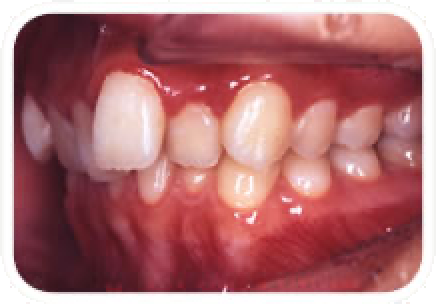

がたがた(叢生)

歯が並ぶ隙間がなくてガタガタの状態です。

特に歯が重なっている部分の歯みがきがしにくく、虫歯や歯周病のリスクが高まり、うまく物が噛めなかったりと色々な障害が生じてきます。